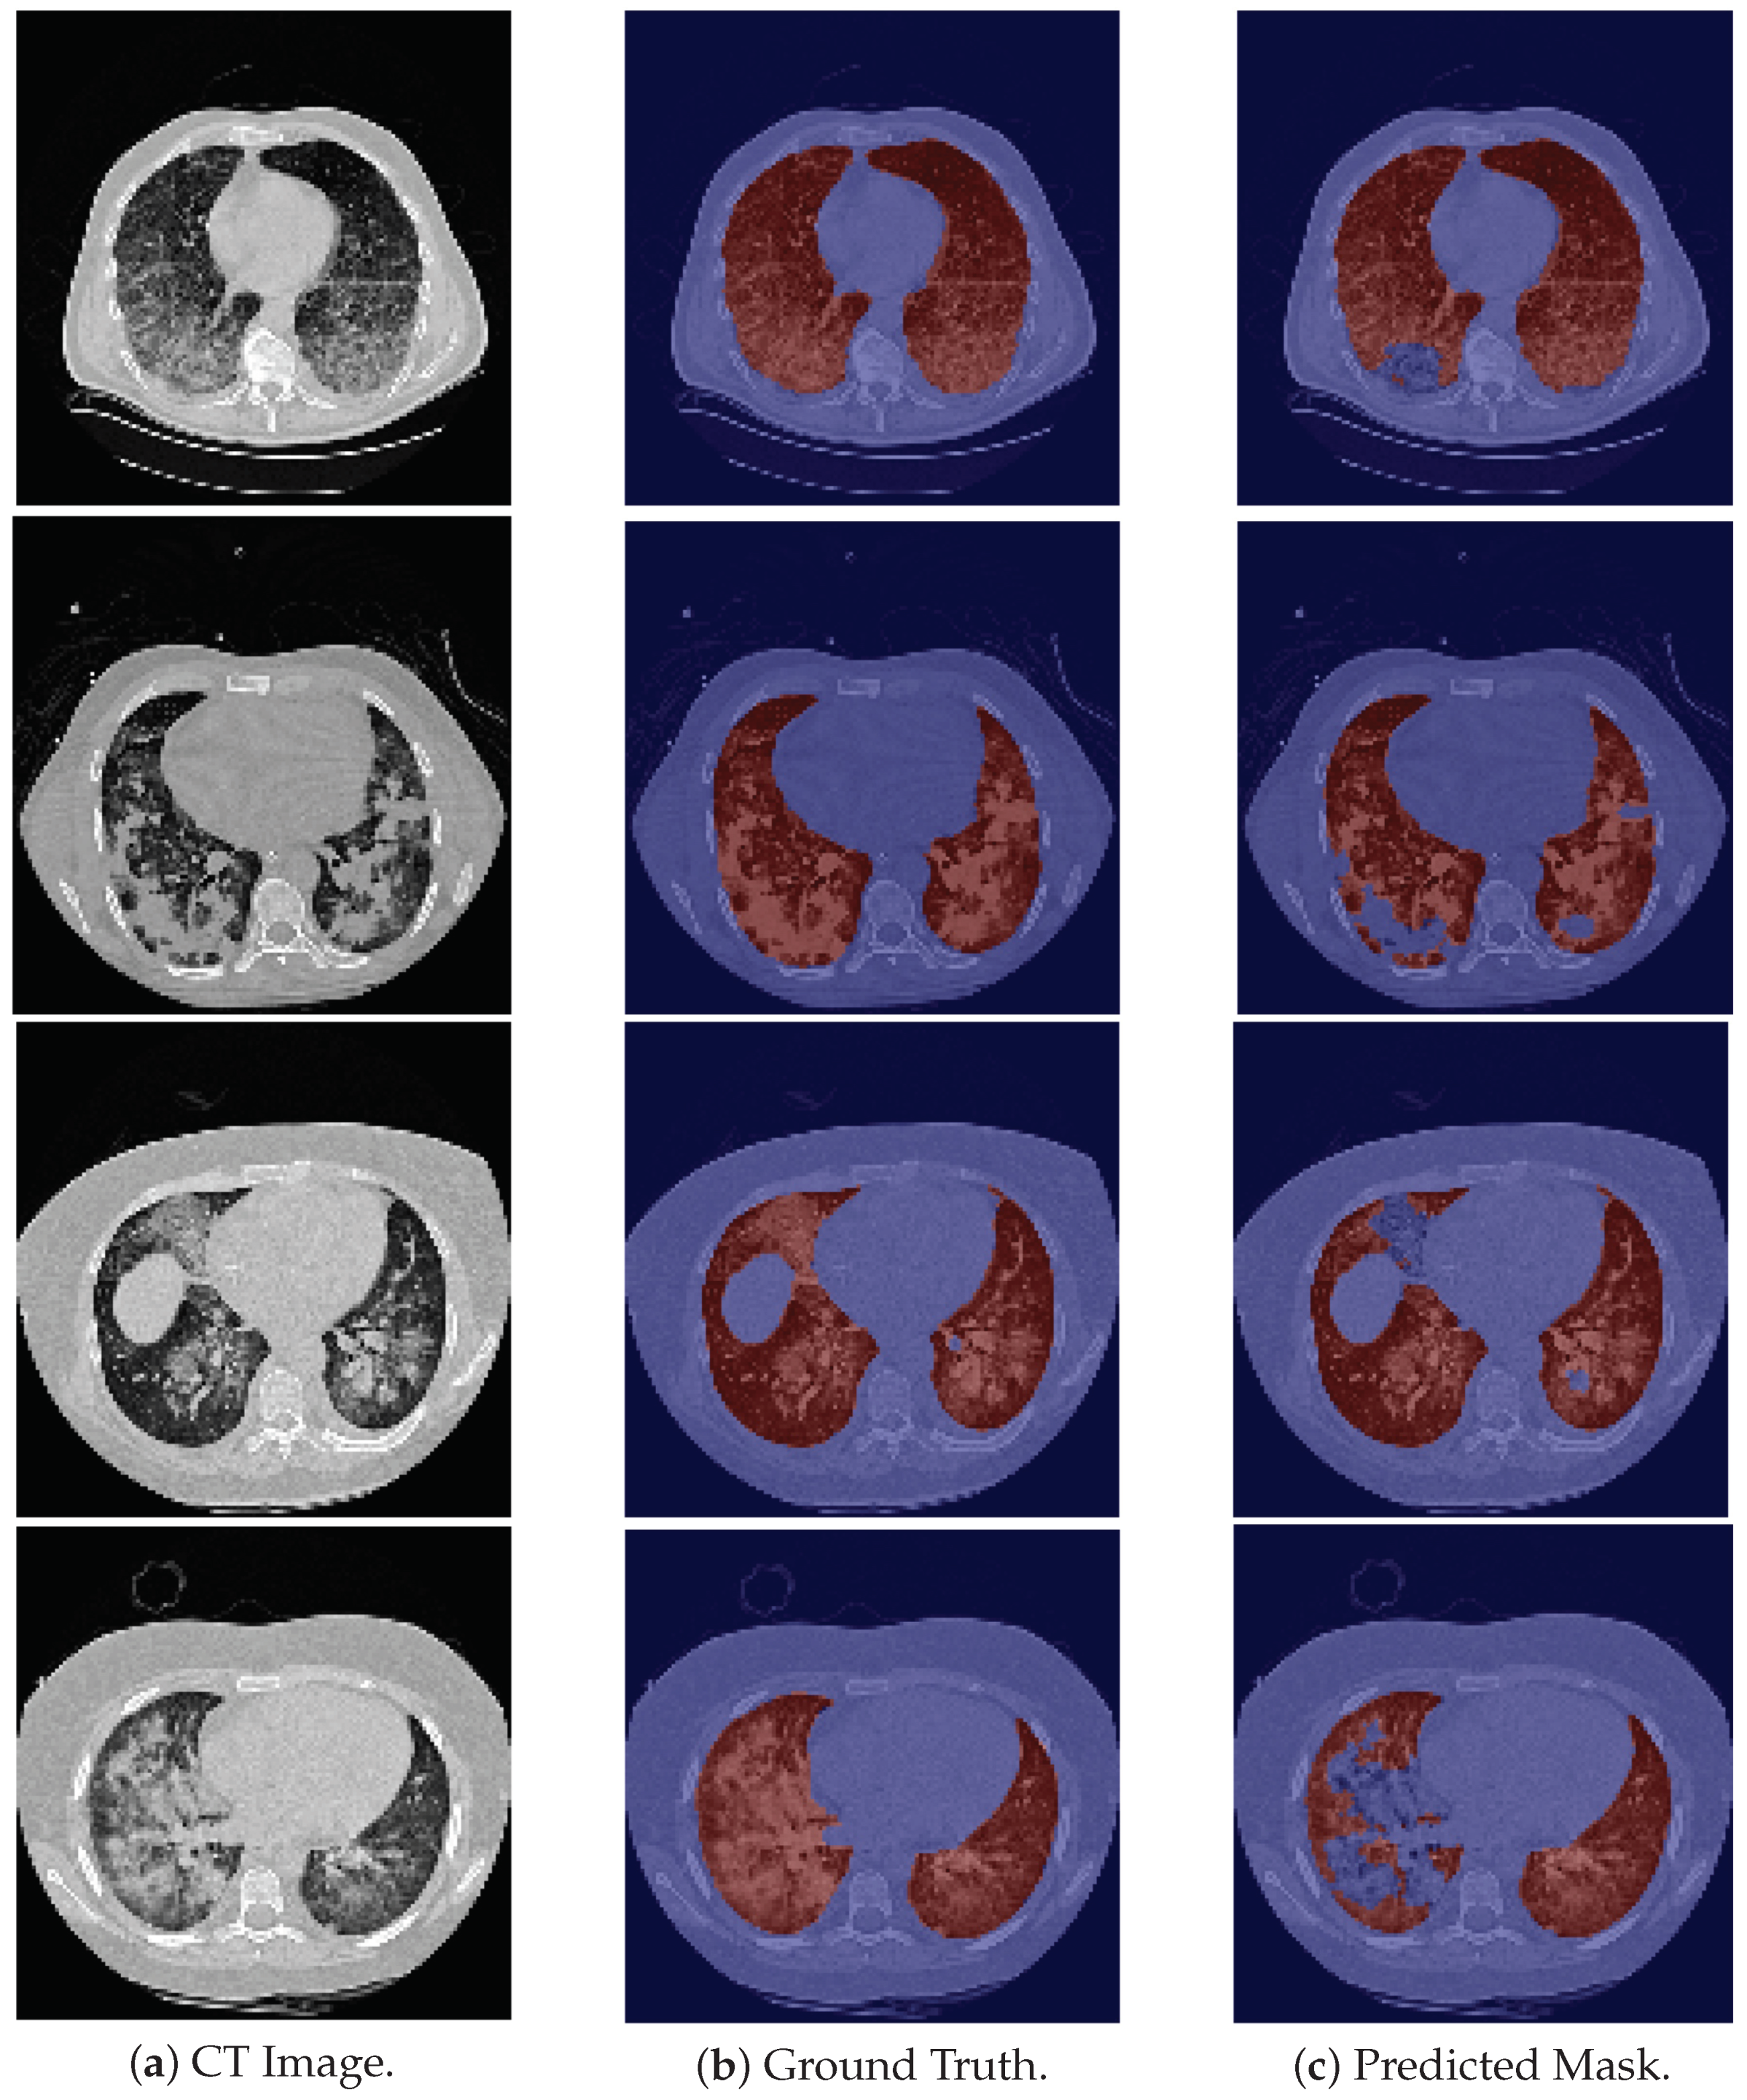

As for the CHUSJ dataset, the model demonstrates, once again, a difficulty in the segmentation of the base of the lung (see the first row of Figure 5). Nonetheless, what contributes most to the decrease in the DSC is the large masses of higher density that are present in the majority of the scans and which the model does not identify. The model correctly segments the surrounding pulmonary tissue and these masses are the only structures that are not included in its predicted masks. Examples of these scans are depicted in the last two rows of Figure 5.

In areas of higher density (“whiter” on the CT image) than the surrounding lung, resulting from involvement by interstitial lung disease or inflammatory/infectious pathology, they are not recognized by the model as lung tissue (see first three rows in Figure 6), although they corresponded to areas of “diseased” lung, involved by interstitial pathology.

In the case of lung neoplasms, something similar happens: the whole healthy lung is properly recognized; however, only the area of the lung mass, which is denser (“whiter”) than the remaining lung, is not properly recognized (see last two rows in Figure 5).

A similar situation occurs in areas of the lung that are even less dense than usual (“blacker” on the CT image) which may also correspond to areas of “diseased” lung, in this case, areas of “air-trapping”, emphysema, etc. (see the last row in Figure 6).

Figure 6. Examples from HUG-ILD dataset. First three rows show cases with higher density that the model does not classify as being lung tissue. Last row shows a darker pulmonary region misclassified by the model.

Figure 5. Examples of CHUSJ images, the ground truth and predicted mask. The first row is an example in which the model fails to correctly segment the pulmonary base; and second and third rows are examples in which the model does not segment the high density tumor masses.

Applsci 12 01959 g005